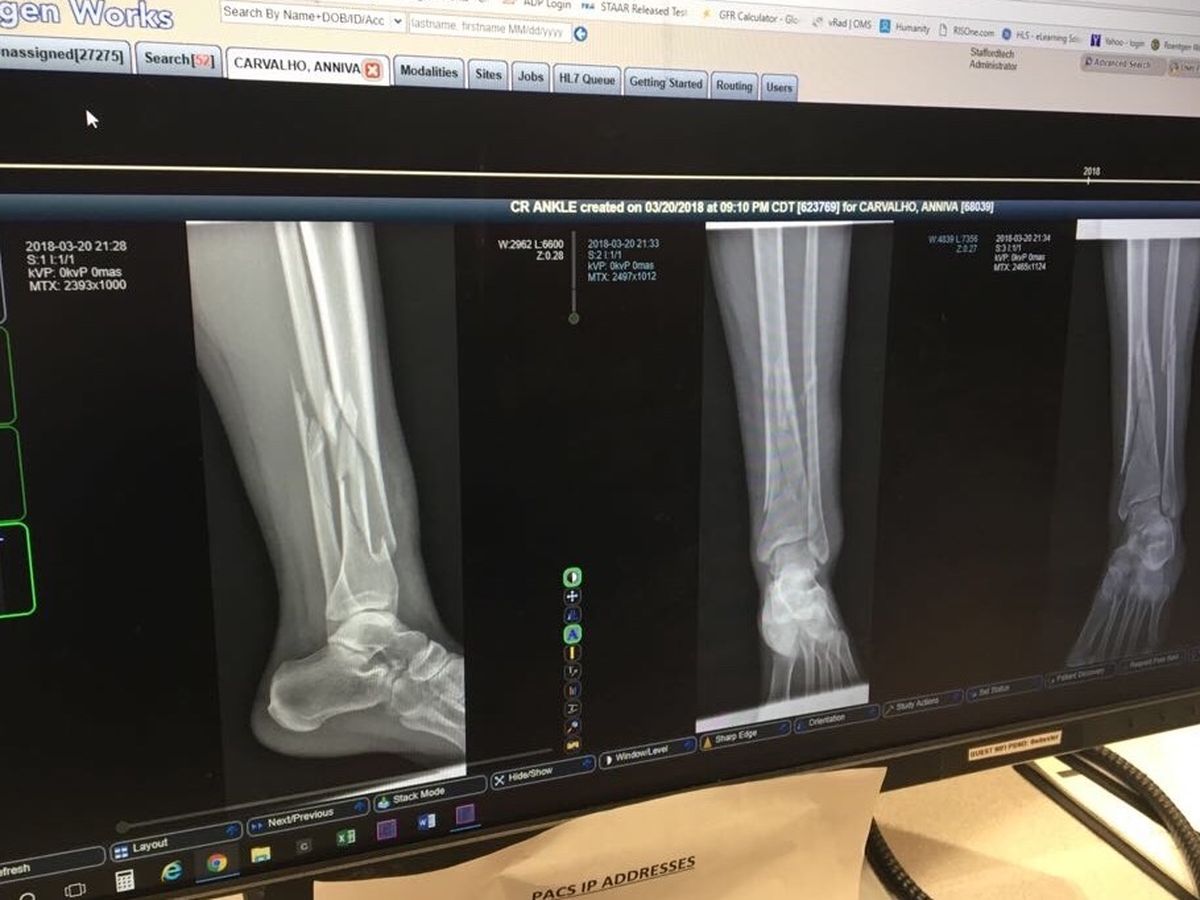

The actual reason I’m doing this is because last night (3/20)  I was riding my bike through a dirt trail and something got caught on my tire and I flipped and fell onto my left leg...It cracked, twisted and dislocated in multiple locations (see photo above). The two bones on the leg are the Fibula & the Tibia...I fractured them so hard that they moved a bone length away from its original location & also cracked into pieces in some parts. The pain has been terrible. But I’m mostly upset that I can’t be “on the run” like I usually am. I have to be bedridden and that is hell to someone who has so much to do. My calendar was full these next couple of weeks...not anymore sadly. It’s like life said...”you’re struggling with $ right now so I’m just gonna throw a broken leg and a medical bill on you right quick”. I am just being honest... I cannot afford my bill.

Update: I did my first surgery today and they added pins to my bones to keep them in place . I feel like bionic woman except with pain in my metal parts ha.